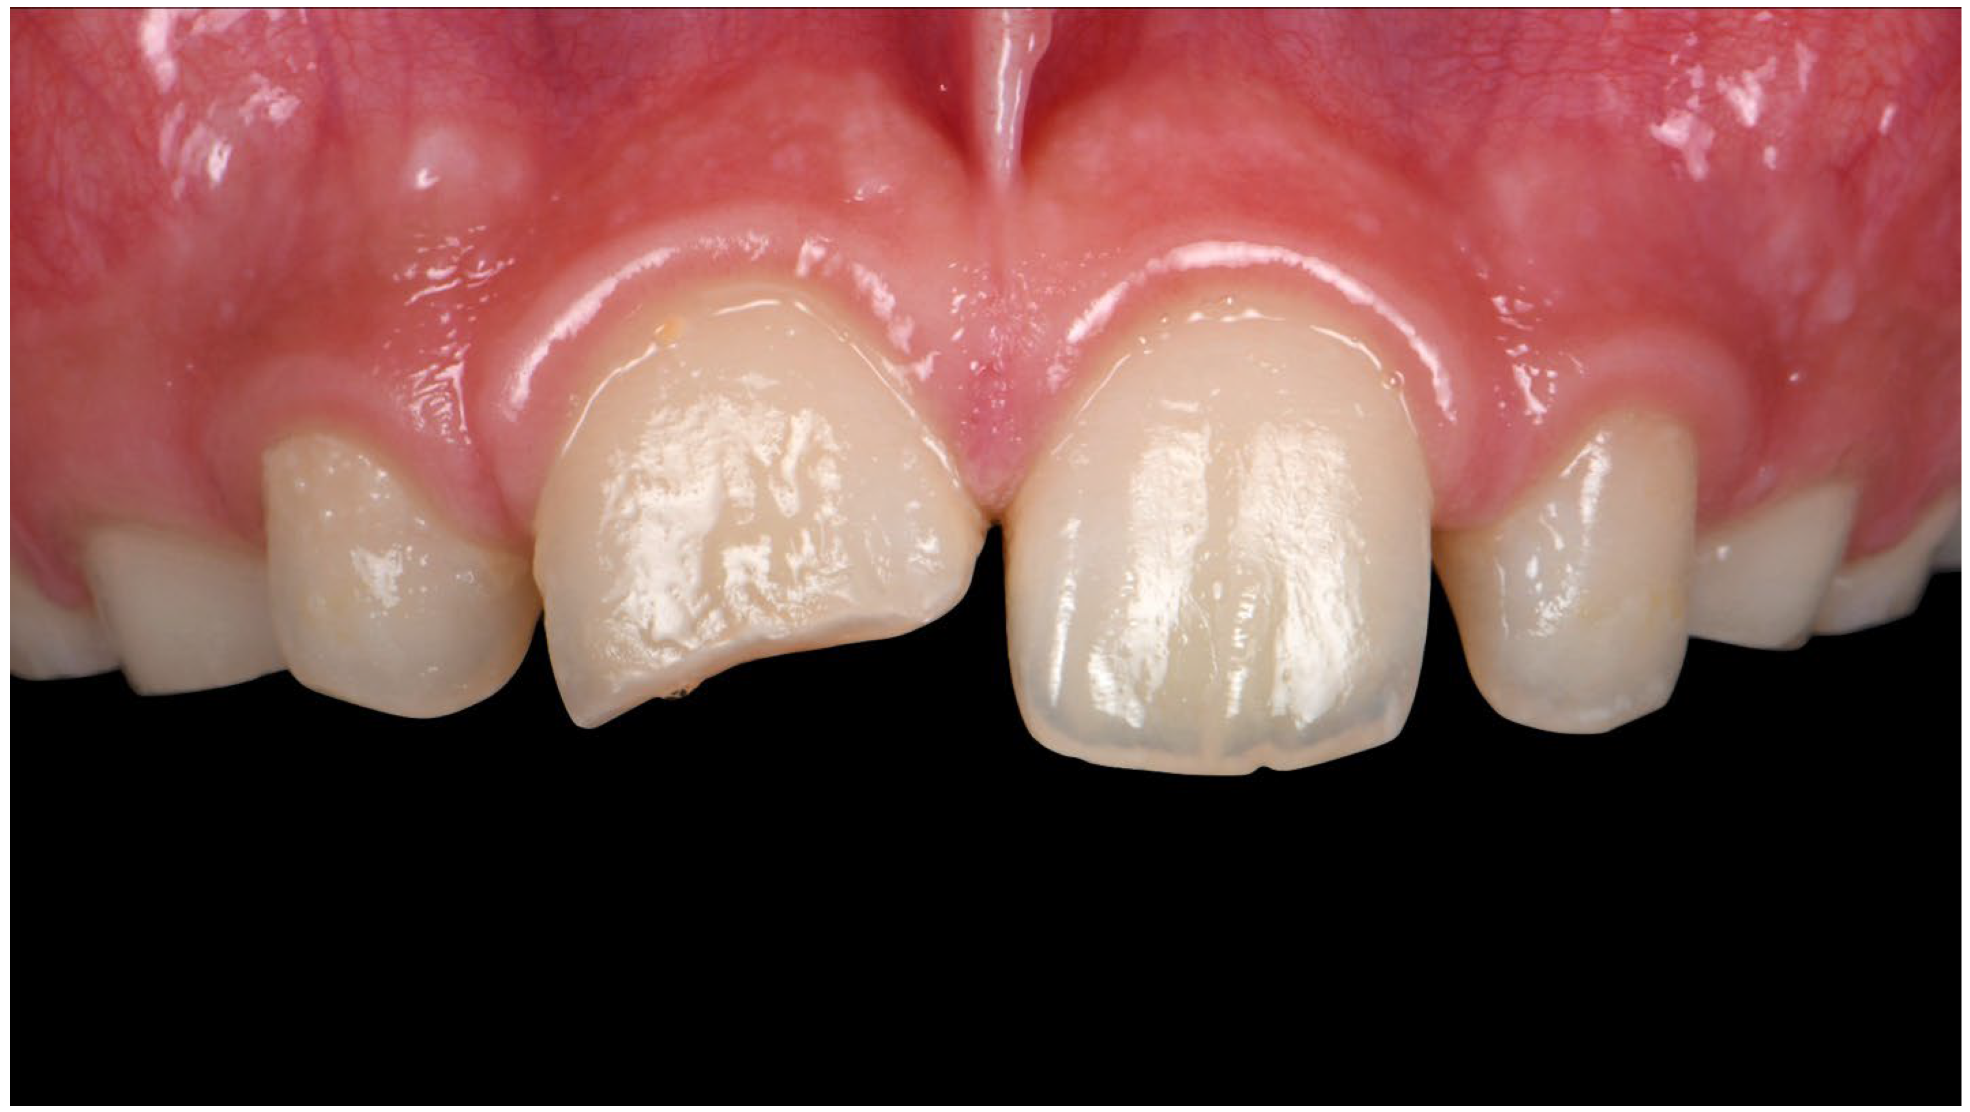

5. Oblique Fractures

- 1.

- Supragingival

5.1. No Pulp Involvement

- Treatment option: Adhesive dentistry.

5.2. With Pulpal Involvement

- Treatment options: Endodontic Treatment and Adhesive dentistry.